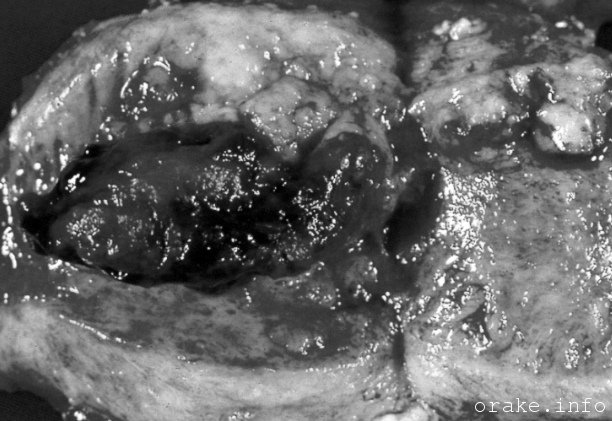

Этот вид наиболее распространенного злокачественного процесса женских органов начинается именно во внутренней оболочке, выстилающей матку. Она называется эндометрием.

В зависимости от того, как клетки выглядят под микроскопом (гистологического вида) различают такие типы ракового заболевания эндометрия матки:

- чаще всего возникает опухоль железистой (секреторной) ткани ‒ аденокарцинома. Ее подвиды представляют: эндометроидный рак, аденоакантома, смешанные клеточные карциномы, коллоидные аденокарциномы, папиллярные, серозные и др.;